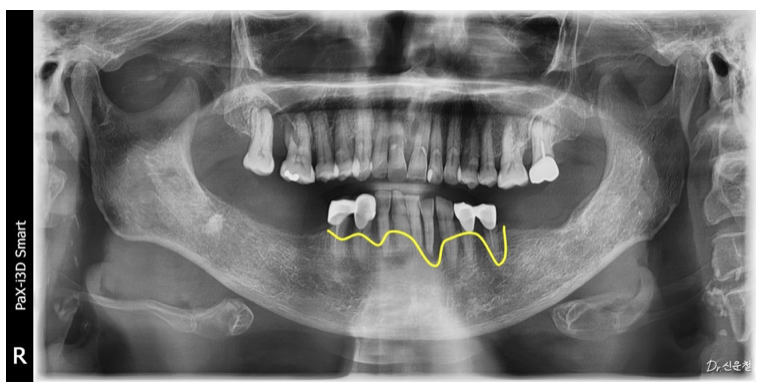

그래서 먼저 아래턱의 뼈 상태를 확인했습니다.

다행히 환자분은

임플란트를 진행할 수 있는 정도의

뼈 상태가 유지되어 있었습니다.